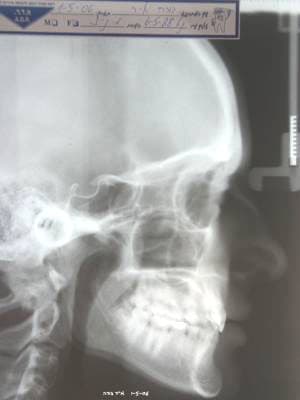

Je me suis permis de rectifier la Rx. pour avoir une idée du profil

@+ Bjc.